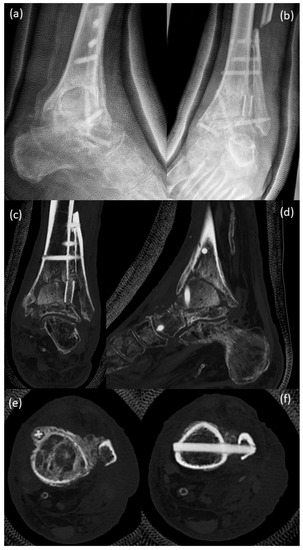

Arthrodesis and Defect Bridging of the Upper Ankle Joint with Allograft Bone Chips and Allograft Cortical Bone Screws (Shark Screw®) after Removal of the Salto-Prosthesis in a Multimorbidity Patient: A Case Report

3. Surgical Procedure

4. Postoperative Rehabilitation

5. Results